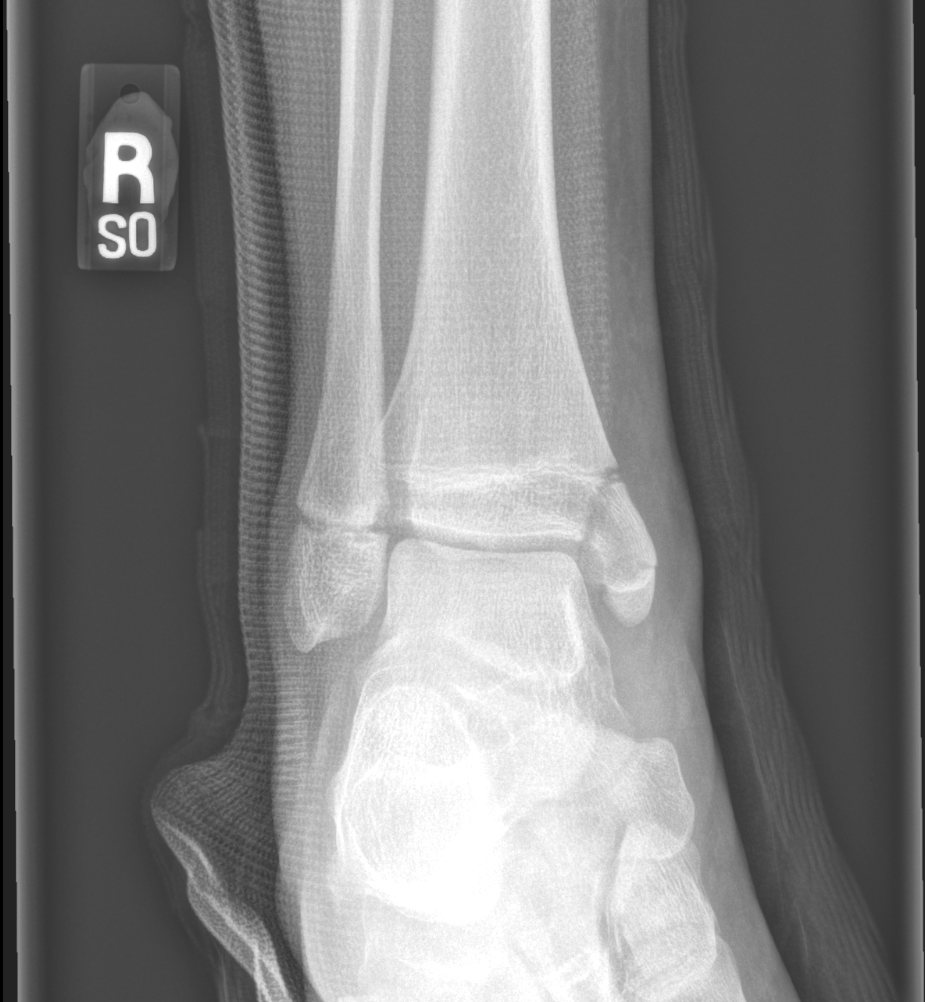

Findings

Bone

Growth plates, ossification centers, apophyses

Joints and alignment